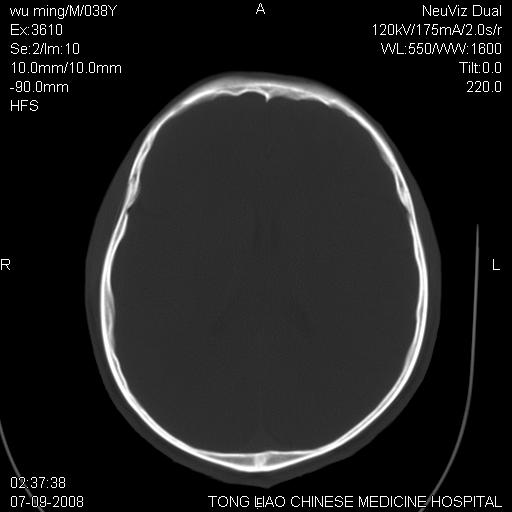

颅底多发骨折。

颅底多发骨折.

颅底多发骨折.上颌骨多发骨折

颅底多发骨折!支持!

考虑:面骨、颅底骨多发骨折,颅内高压(脑肿胀)。

1)颅底骨及颌面骨多发性骨折。2)副鼻窦及双侧鼻腔积血。

多发性颅骨骨折